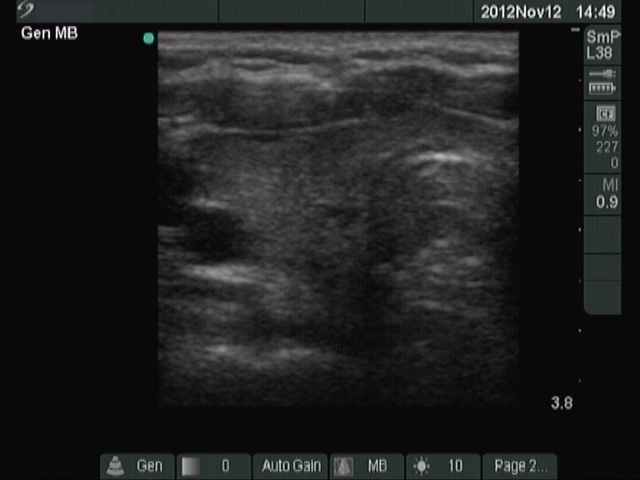

Subacute granulomatous thyroiditis - case 1285

Follow-up - 4 months after initial investigation (ultrasonographic picture 2)

Right lobe, longitudinal scan.